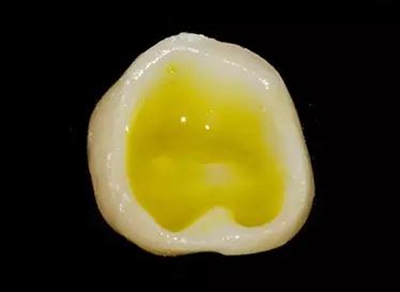

牙體制備完成后的牙合面觀

牙合面觀察牙體預備之后的情況。

軸壁按要求預留0.8 mm 寬度。